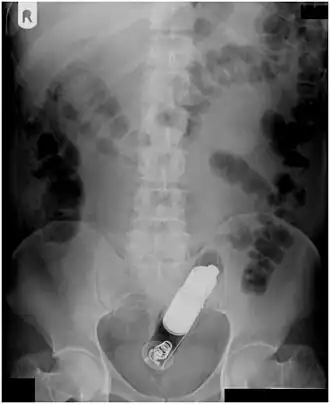

Radiograph of a male abdomen with a vibrator inside the rectum

Usually, several radiological images are recorded in order to pinpoint the precise place and depth of the foreign body. This is usually done by X-ray. Foreign bodies made from low-contrast material (e.g. plastics) may necessitate medical ultrasound or a CT scan.[29] Magnetic resonance imaging is contraindicated, especially if the foreign body is unknown. Foreign rectal bodies may penetrate deep into the colon, in certain circumstances up to the right colic flexure.[10]